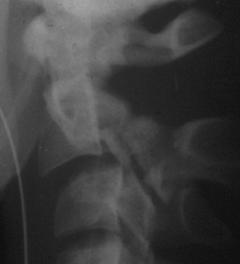

FRACTURA - LUXATIE T12 FRACTURA COMPLEXA DE COLOANA

VERTEBRALA LOMBARA